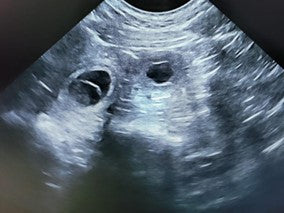

Embryonic deaths are not uncommon. It is reported that in 10-11 % of pregnancies embryonic deaths happen. In this article Merja Dahlbom, Doctor of Veterinary Medicine and ECAR Diplomate, explains Canine Embryonic Death.